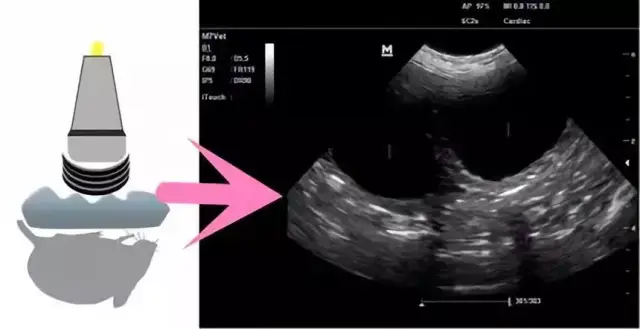

小动物超声成像原理示意图(图中1为充满液体的子宫;2子宫壁;3

图片尺寸640x328